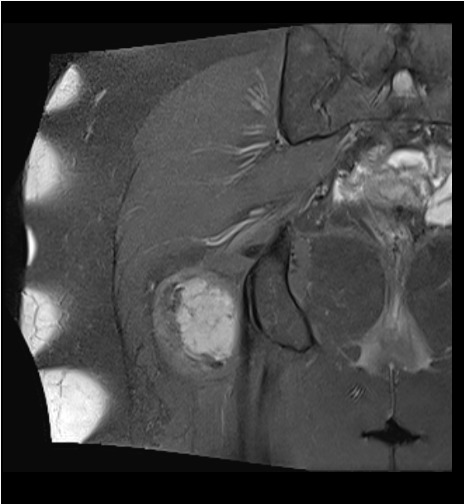

Sarcoma Sinovial: é uma doença maligna das partes moles que é mais comum nas regiões justarticulares, como nos joelhos e quadris de adolescentes e jovens adultos. Boa resposta a quimioterapia e radioterapia, a abordagem multidisciplinar é fundamental para bons resultados.